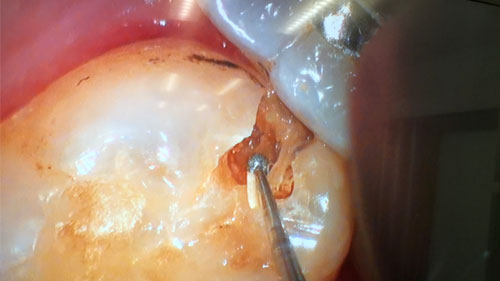

当院の顕微鏡歯科では、肉眼やゴーグル型拡大鏡の8~30倍もの拡大率があるマイクロスコープを使用します。

これにより歯科医師の経験や勘だけではなく、歯を削る時や被せ物を装着する時、つめ物を接着する時なども、細部までしっかり確認することが可能となります。

歯の神経が残っている場合はできるだけ削らず、歯の神経を残すことを心がけ、歯へのダメージを最大限に抑えた治療をすることができます。